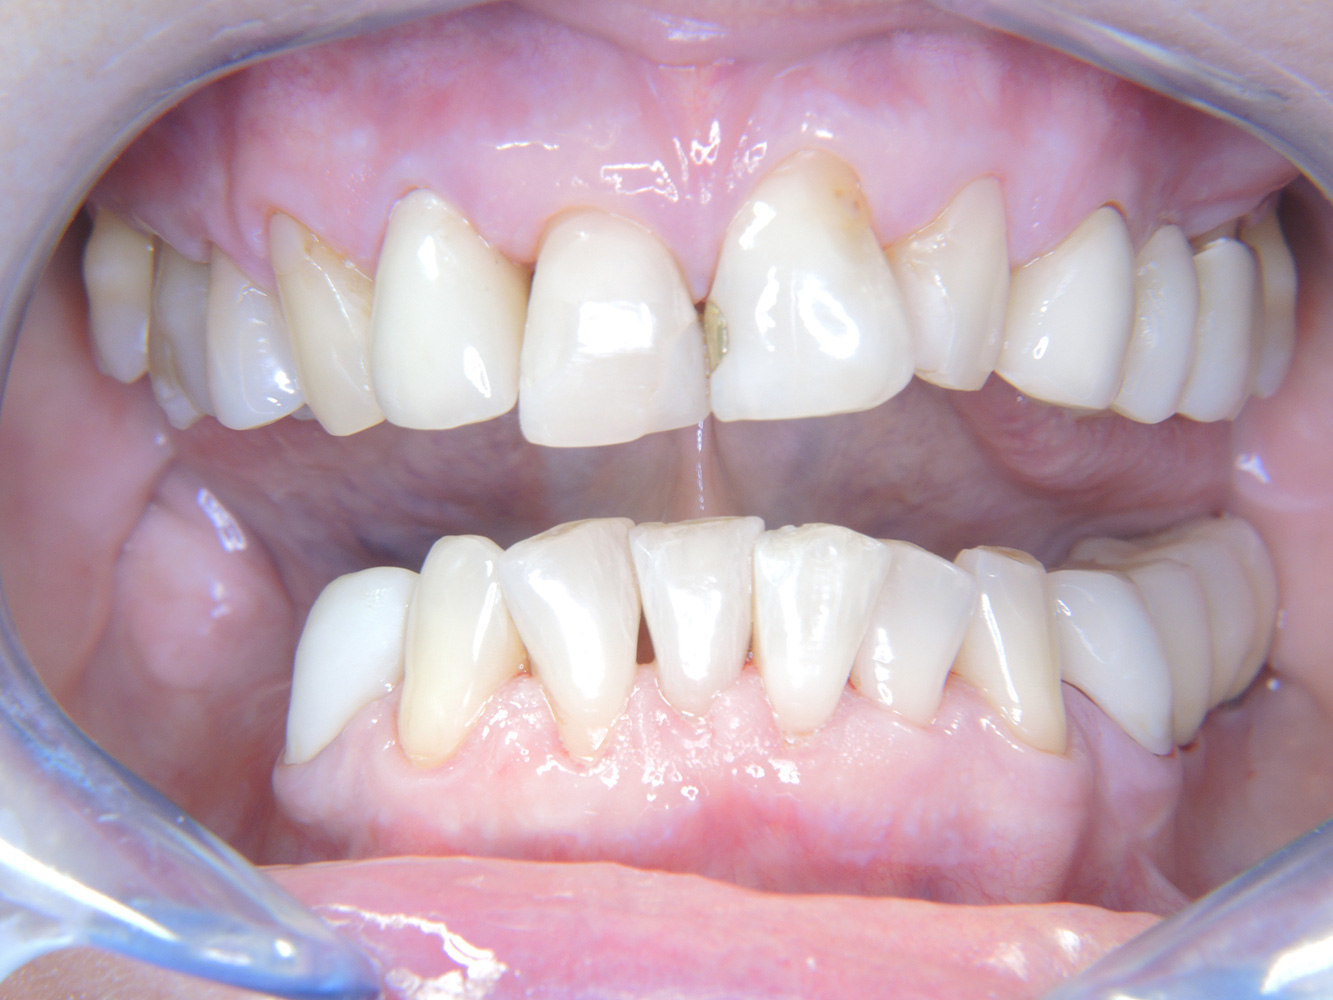

The 68-year-old patient has no general health conditions and is not taking any medication that may be relevant to her oral health, and her lifestyle does not pose any particular risk. The patient has two dental implants (3rd quadrant, for five years) and a previous case of periodontal disease (stage IV, grade B periodontitis) with tooth loss. Currently the periodontal conditions are stable. However, periodontitis significantly increases the biological complications of implantations and there is a risk of implant loss (21). Four recommendations can be determined for the prophylaxis session.

As the patient does not have any particular risk factors with specific dental implications, the requirements determined from her current state of oral health are crucial. Here, it is recommended that a thorough assessment of periodontal condition be carried out once a year. This will ensure that any potential progression of the previous periodontal disease or development of peri-implantitis can be responded to in good time.

Despite the stable conditions, it is also crucial for the instructive/motivational discussion to be conducted with this patient. Particular attention should be paid to teaching the patient how to care for the implants correctly. Here in particular, good at-home maintenance can have a significant impact on the long-term stability of oral and implant health.